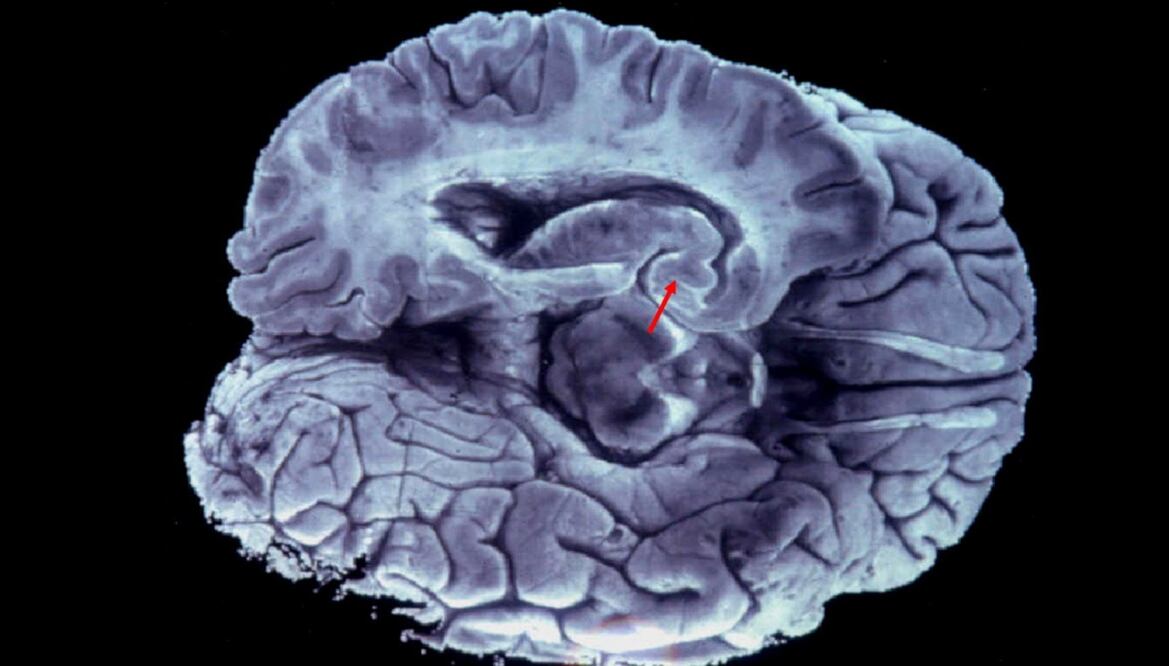

Este anticuerpo monoclonal parece concentrarse en la destrucción de placas formadas por algunas proteínas, conocidas como "beta-amiloides", en el cerebro de los pacientes. Al comprimir las neuronas, estas placas son uno de los grandes factores de la enfermedad de Alzheimer.

En los últimos años hay otra dirección que los laboratorios están explorando: el comportamiento anormal de otra categoría de proteínas, las denominadas tau , también presentes en las neuronas.

En los enfermos de Alzheimer, esas proteínas se concentran como racimos y acaban por provocar la muerte de la célula. Es ese aspecto el que interesa a AC Immune y Roche.